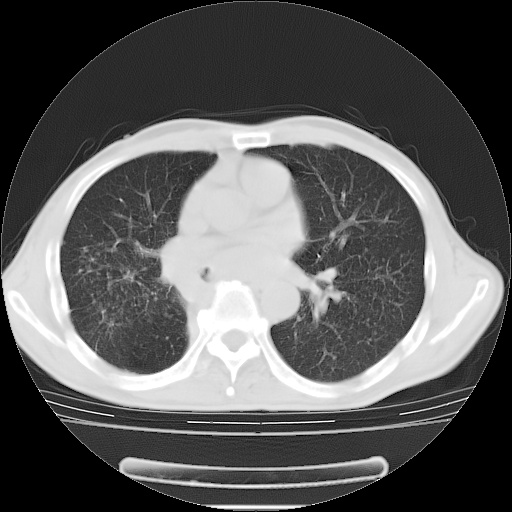

男性患者,63岁。右侧胸背部疼痛2月,加重一周。

考虑:右肺中央型肺癌并右肺下叶不张;两肺尖继发性肺结核。

还有纵隔多处肿大淋巴结及肋骨的改变、两肺多发结节灶。

右肺下叶支气管狭窄闭塞,右下肺不张,气管前间隙淋巴结肿大,两上肺散在分部粟粒灶,沿肺血管支气管束分部,血管支气管束走形较为光滑。考虑右肺中心型肺癌合并肺不张,纵隔淋巴结转移,两上肺癌性淋巴管炎